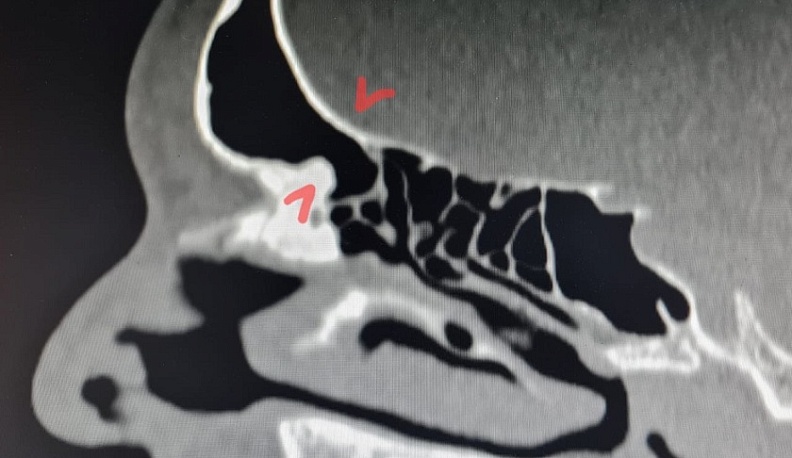

Фото: Елена Разумеева/Вконтакте. На снимке пазуха с блокированными путями оттока.

«Сложность операции заключалась в необходимости выполнения сразу нескольких вмешательств на соседних пазухах, опасности повреждения стенок пазухи и проникновения в полость черепа, малого пространства для работы инструментов и необходимости удаления большого объёма костной ткани в полости носа и пазух под контролем эндоскопа», - сообщила главврач.